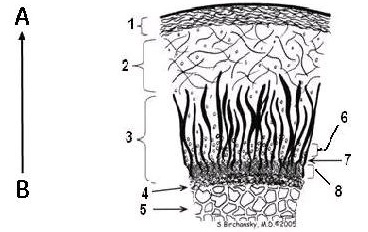

Collagen composition

The collagen in the radial zone of articular cartilage, close to the subchondral bone is highly ordered, with only small quantities of mobile water. By contrast, the collagen in the transitional zone is more randomly oriented, with increased mobile water and more prolonged T2 values. Increased T2 relaxation times within cartilage have been associated with matrix damage, particularly loss of the orientation of the collagen matrix.

| Callouts | Description |

|---|---|

| A | Longer T2 values |

| B | Shorter T2 values |

| 1 | Superficial Zone |

| 2 | Transitional Zone |

| 3 | Radial Zone |

| 4 | Subchondral bone |

| 5 | Cancellous bone |

| 6 | Non-calcified cartilage |

| 7 | Tidemark |

| 8 | Calcified cartilage |

When the cartilage matrix breaks down due to osteoarthritis, the following occurs:

Disruption of collagen --> increased mobility of water -->prolongation of T2 relaxation times.